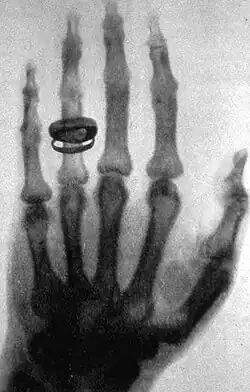

- X-rays. A form of electromagnetic radiation with a wavelength in the range of 10 to 0.01 nanometers, corresponding to frequencies in the range 30 to 3000 PHz (1015 hertz). X-rays are primarily used for diagnostic medical and industrial imaging as well as crystallography. X-rays are a form of ionizing radiation and as such can be dangerous.